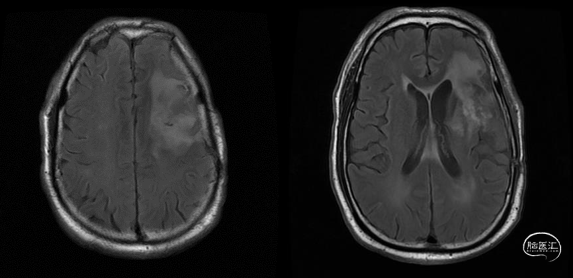

术前核磁(2020-03),左侧额岛叶肿块,信号不均匀,其内可见出血和坏死,占位效应明显,周围见水肿:图示。

增强MR(外院),可见不均匀明显强化,中间可见不强化坏死区,边界不清:图示。

入院前头MRI(2020-3):左侧额岛叶肿块,信号不均匀,其内可见出血和坏死,占位效应明显,周围见水肿。考虑左额岛叶肿瘤(高级别脑胶质瘤可能性大)。于2020年4月行左额岛叶占位性病变切除术。术中见肿瘤组织位于左侧额中回及额下回后部,大小约4m×5cm×5cm,呈烂鱼肉样,色灰红,质软,部分坏死,血运中等,边界不清,侵犯左侧岛叶向下挤压颞叶。显微镜下沿肿瘤周边胶质增生带完整切除肿瘤。术后48小时内复查头MRI平扫、加强,影像显示术腔边缘不规则线样强化,靠近放射冠及侧脑室壁强化明显,可疑少许残存。